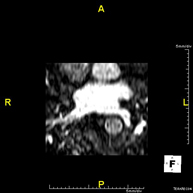

Angio-RM de venes pulmonarsProva diagnòstica no invasiva que consisteix en l'estudi del patró de drenatge de les venes pulmonars mitjançant l'ús d'un camp electromagnètic i ones de ràdio (amb un emissor i un receptor) i de contrast paramagnètic (Gadolini). No utilitza radiació ionitzant. Està indicada com a mapa angiogràfic previ en pacients que seran sotmesos a l'ablació de les venes pulmonars i pel seu seguiment, per descartar l'aparició d'estenosi.